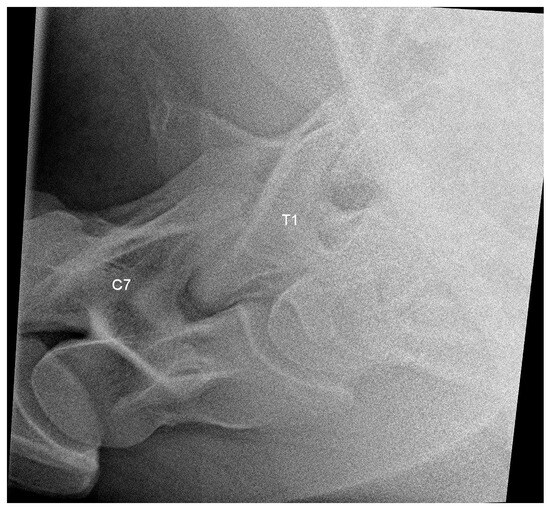

2.3. Radiographic Method

2.4. Classification System